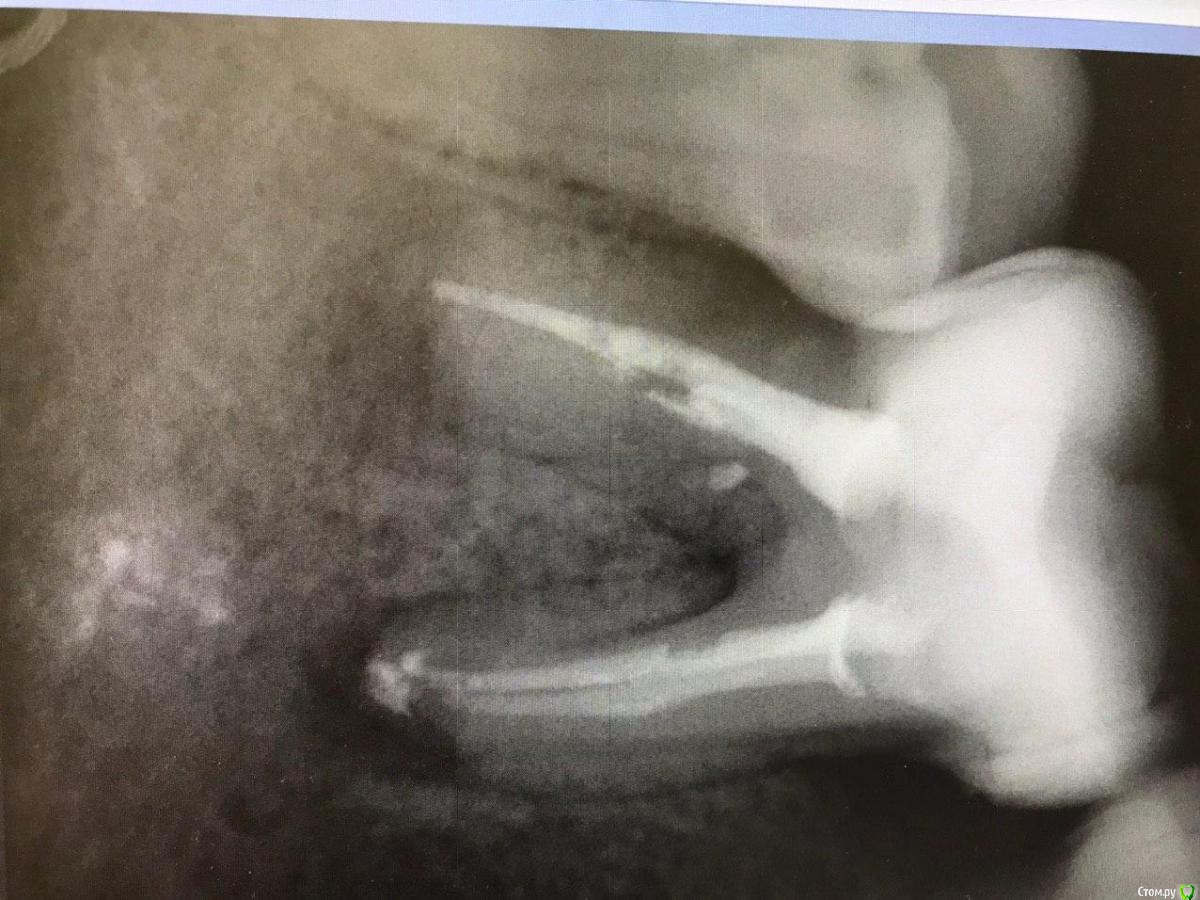

1586Doc Опубликовано 8 февраля, 2020 Поделиться Опубликовано 8 февраля, 2020 5 месяцев назад обратилась пациентка с симптоматикой периодонтита. Оценили, попробовали. Пломбировка вертикалка. 5 месяцев и контроль, боли нет, подвижности тоже. 2 Ссылка на комментарий

1586Doc Опубликовано 10 февраля, 2020 Автор Поделиться Опубликовано 10 февраля, 2020 (изменено) А где контроль на сегодня? При таком качестве снимков оценить будет тяжело.первые 2 фото снимки 9 месяц назад, до ревизии Изменено 10 февраля, 2020 пользователем 1586Doc Ссылка на комментарий

1586Doc Опубликовано 10 февраля, 2020 Автор Поделиться Опубликовано 10 февраля, 2020 (изменено) Имхо пока не вижу успеха. ((ну если еще с 46 я могу понять, 45 явно деструкция в разы меньше. 100% месяца через 3-4 назначу клкт Изменено 10 февраля, 2020 пользователем 1586Doc Ссылка на комментарий